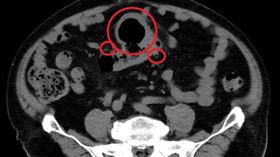

反覆腹痛逾1年才就診 醫:最大8公分了

北部一名七旬男性1年多來飽受不明腹痛之擾,大腸鏡檢查...

糞便有血=罹癌?虛驚一場的大腸憩室出血

58歲的劉小姐因為糞便有血數日,擔心自己是罹患大腸癌...